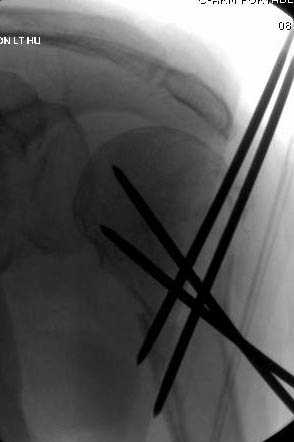

Наличие рентген контроля (ЭОП) помогает во время

репозиции и фиксации, но многие коллеги умудряются без рентгена фиксировать несколькими спицами перкутанно.

Наш недавний случай перкутанной фиксации "методом

Сиэтла" спицами 2.8 мм с резьбой на конце.